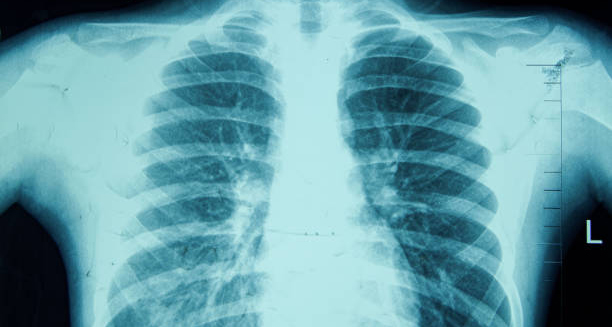

3. Chest X-Ray or CT Scan | Diagnosis of Chronic Obstructive Pulmonary Disease

Imaging tests can rule out other conditions like lung cancer, tuberculosis, or heart disease. They may show lung overinflation, flattened diaphragms, or enlarged air spaces typical of emphysema.